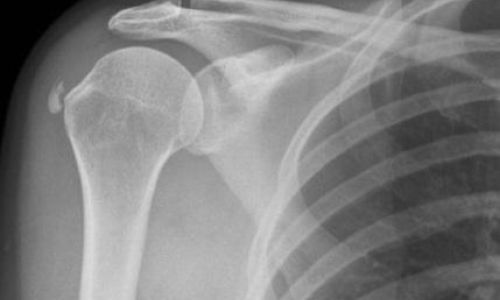

Η ασβεστοποιός τενοντίτιδα του ώμου αποτελεί μια συχνή πάθηση των ενηλίκων. Η πάθηση χαρακτηρίζεται από την εμφάνιση ασβεστώματος με συνοδό φθορά στους τένοντες των μυών του στροφικού πετάλου του ώμου (υπερακάνθιος και υπακάνθιος). Η πάθηση είναι κυρίως ιδιοπαθής. Εμφανίζεται συχνότερα σε γυναίκες και κυρίως σε άτομα της ηλικιακής ομάδας από 30-60 ετών. Στατιστικά συνδέεται με την ύπαρξη 2 συνοδών νοσημάτων, του σακχαρώδη διαβήτη (Σ.Δ.) και του υποθυρεοειδισμού. Η κλινική εικόνα είναι η εξής. Ο ασθενής εμφανίζει έντονο άλγος στην περιοχή του ώμου με συνοδό μείωση του εύρους κίνησης της άρθρωσης. Το άλγος μπορεί να είναι και νυχτερινό ενώ η αδυναμία της κίνησης μπορεί να οδηγήσει στη δημιουργία συμφύσεων στον ώμο και εμφάνισης του συνδρόμου παγωμένου ώμου (frozen shoulder).

Η διάγνωση επιβεβαιώνεται συνήθως με μια απλή ακτινογραφία ενώ σε περιπτώσεις που χρειάζεται αρθοσκοπική αποκατάσταση γίνεται και μαγνητική τομογραφία ώμου.

Η θεραπεία είναι φαρμακευτική με χρήση μη στεροειδών αντιφλεγμονωδών φαρμάκων, φυσικοθεραπείες με μυϊκή και κινητική ενδυνάμωση της ωμικής ζώνης ενώ πλέον η πιο σύγχρονη αντιμετώπιση γίνεται με τις νέες βιολογικές θεραπείες, με έγχυση πλάσματος πλούσιο σε αιμοπετάλια (prp injection).

Σε εμμένουσες καταστάσεις που είτε τα συντηρητικά μέσα δεν έχουν εξαλείψει πλήρως το πρόβλημα, είτε σε καταστάσεις που πλέον δυσκολεύουν τις απλές καθημερινές δραστηριότητες του ασθενούς, η λύση είναι η ελάχιστα επεμβατική χειρουργική μέθοδος του ορθοσκοπικού καθαρισμού της ασβέστωσης. Η μέθοδος είναι γρήγορη, ακριβής, με ελάχιστο χρόνο παραμονής στο νοσοκομείο (ημερήσια νοσηλεία), ενώ ο ασθενής ανακουφίζεται άμεσα από τα συμπτώματα επιστρέφοντας γρήγορα στις καθημερινές του δραστηριότητες.